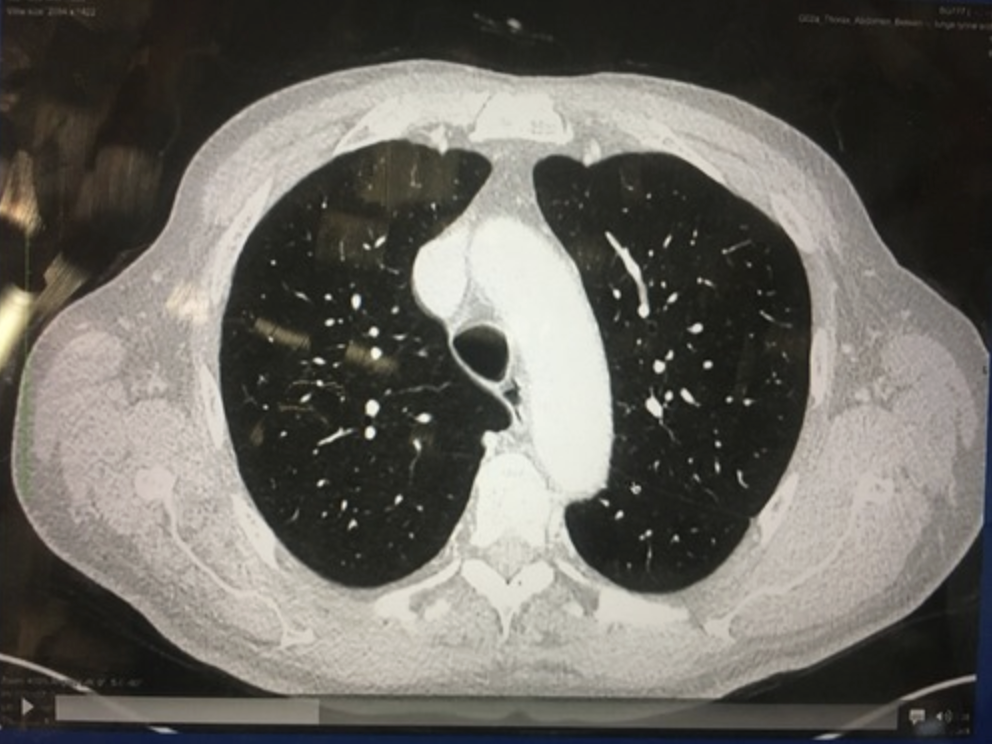

La crosse aortique passe de quel côté de la trachée?

A

Elle passe à gauche, car le coeur est lui aussi à gauche